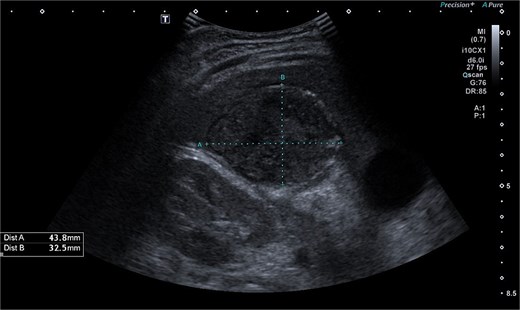

Abdominal ultrasonography identified a pathological, dense fluid collection in the right upper quadrant measuring 44 × 33 × 45 mm, located adjacent to segment VI of the liver (Fig. 1). The findings suggested an inflammatory lesion, possibly a hepatic abscess secondary to appendicitis with an atypically directed appendix. Empiric treatment with third-generation cephalosporins and metronidazole was initiated.

Abdominal ultrasonography imaging of pathological dense fluid collection adjacent to liver segment VI.